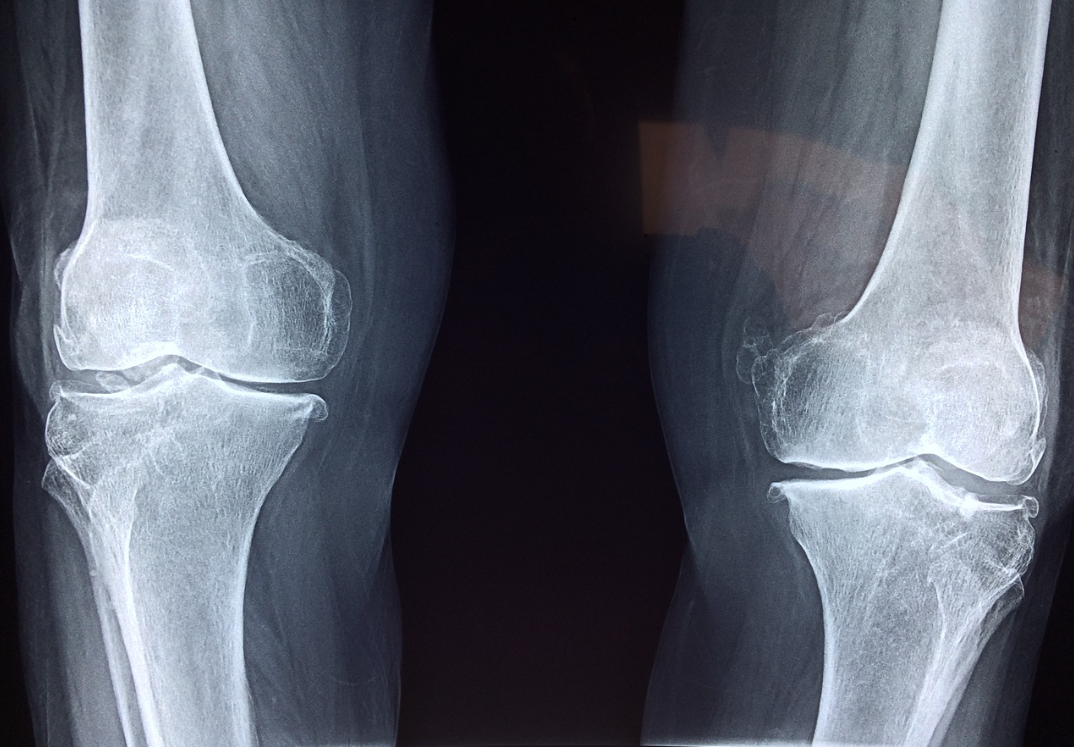

콘드로이친은 퇴행성 관절염(골관절염) 환자들에게 특히 유익합니다. 연구에 따르면 콘드로이친을 꾸준히 복용한 사람들은 관절 통증이 줄어들고, 일상생활에서의 움직임이 편해졌다고 보고했어요. 특히 무릎, 엉덩이, 손목 관절의 통증 개선에 효과적입니다.

연골은 관절을 보호하는 쿠션 역할을 하지만, 나이 들수록 마모되기 쉽습니다. 콘드로이친은 연골의 분해를 억제하고, 연골 세포의 재생을 촉진해 관절 건강을 지키는 데 도움을 줍니다.

콘드로이친은 항염증 작용을 통해 관절 주변의 염증을 줄여줍니다. 이는 관절염으로 인한 붓기와 불편함을 완화하는 데 기여하죠.